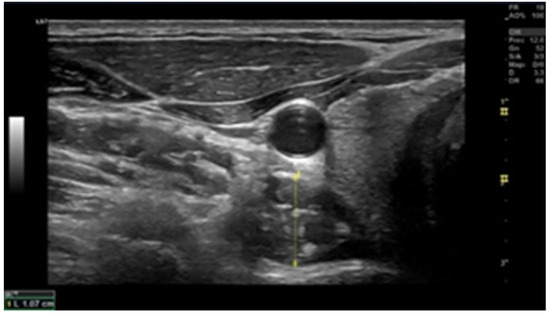

2.6. Muscle Thickness